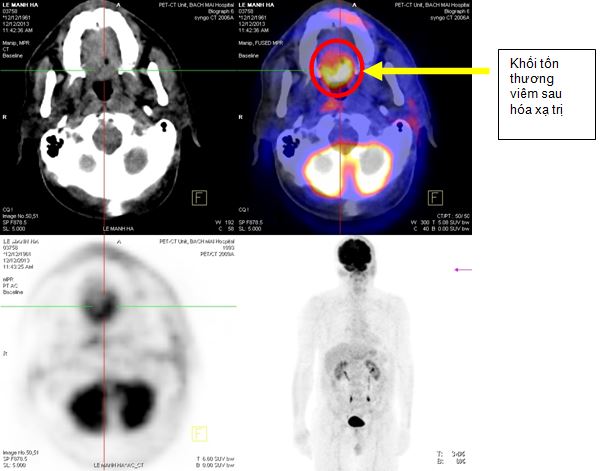

+ Tháng 12 năm 2013, bệnh nhân được chup PET/CT lần 2 sau khi kết thúc xạ trị và 4 đợt hoá trị. Trên hình ảnh PET/CT cho thấy: vùng đáy lưỡi có khối tăng hấp thu F-18 FDG, kích thước 3,9x4,3x3,0cm, theo dõi tổn thương viêm sau xạ trị. Không thấy hạch cổ tăng hấp thu F-18 FDG bất thường.

Hình 6. Hình ảnh PET/CT sau xạ trị 70Gy và 4 đợt hoá trị